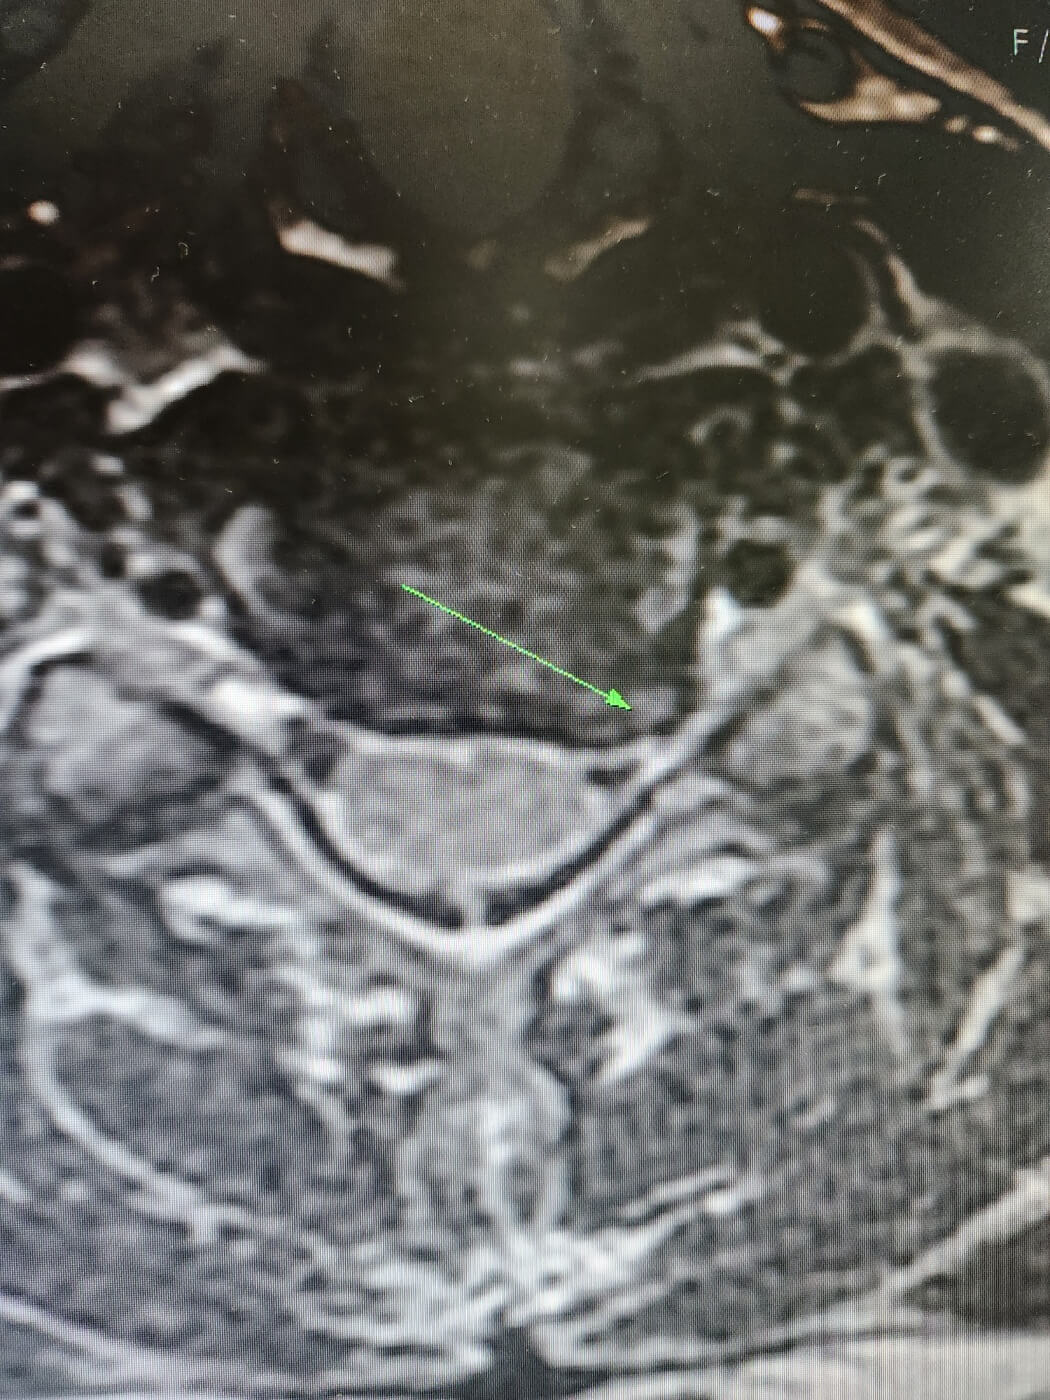

아무튼 작년 3월 터진목 상태는 이랬다.

![]() |